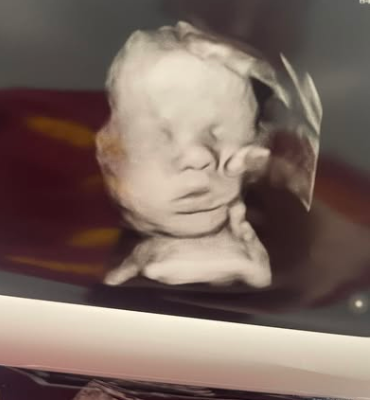

Mutter sieht „Hand Gottes“, die Kopf ihres Babys im Ultraschall hält

Symbolfoto: Shutterstock In dem, was als modernes Wunder bezeichnet wird, sagt eine Mutter aus dem US-Bundesstaat Kentucky, ihr ungeborenes Baby sei von der „Hand Gottes“ berührt worden – und sie hat den Ultraschall, um es zu beweisen. Im April 2022…